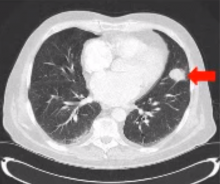

This video presents the case of an 82-year-old male with history of HTN, atrial fibrillation, and skin cancer. He had recently quit smoking after a 30 pack per year history. The patient presented with hemoptysis and investigation revealed a 3 cm spiculated mass in the lingula, which was a concern for malignancy. A CT scan did not reveal any additional pathology, and a PET/CT scan showed avid uptake limited to the mass. Pulmonary function was adequate to permit a surgical resection. Pre-operative cardiac risk stratification was performed.